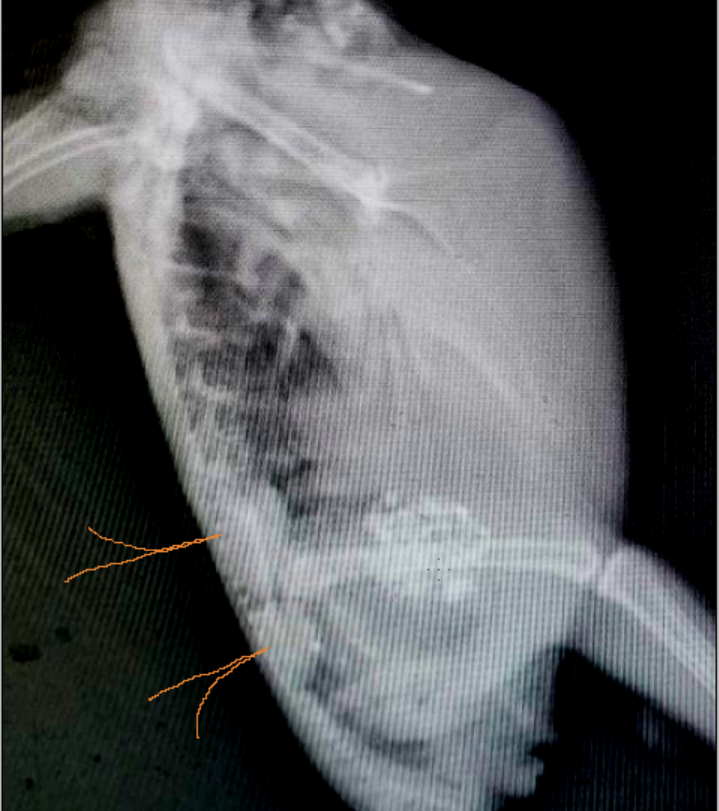

Зравствуйте. Переделали ренген. Помет при отмене всех лекарств лучше. Но картина на ренгене нет

20221009_124542.jpg

20221009_124621.jpg

но сейчас я сделала латеральную проекцию.

да, почки сильно не в порядке.

и голова, и хвост- очень яркие.

714019041_.thumb.png.ee30528b9ae2623773cfe7b526d9c343.png